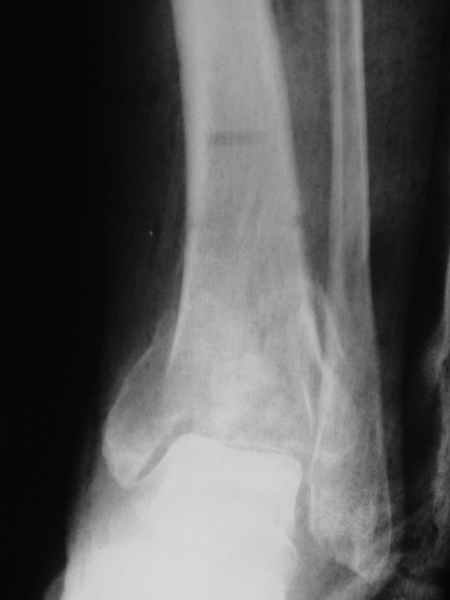

Ортопедия и травматология Отправлено Roberto Biscione 22 Сентябрь 2004, 20:12

Female. 65 years old. 2 years ago trimalleolar fracture left ankle. First ORIF failed. Second ORIF with autologous graft at the fibular fracture was complicated by infection. The X-ray pictures show the actual situation. What are the suggestions of the group?